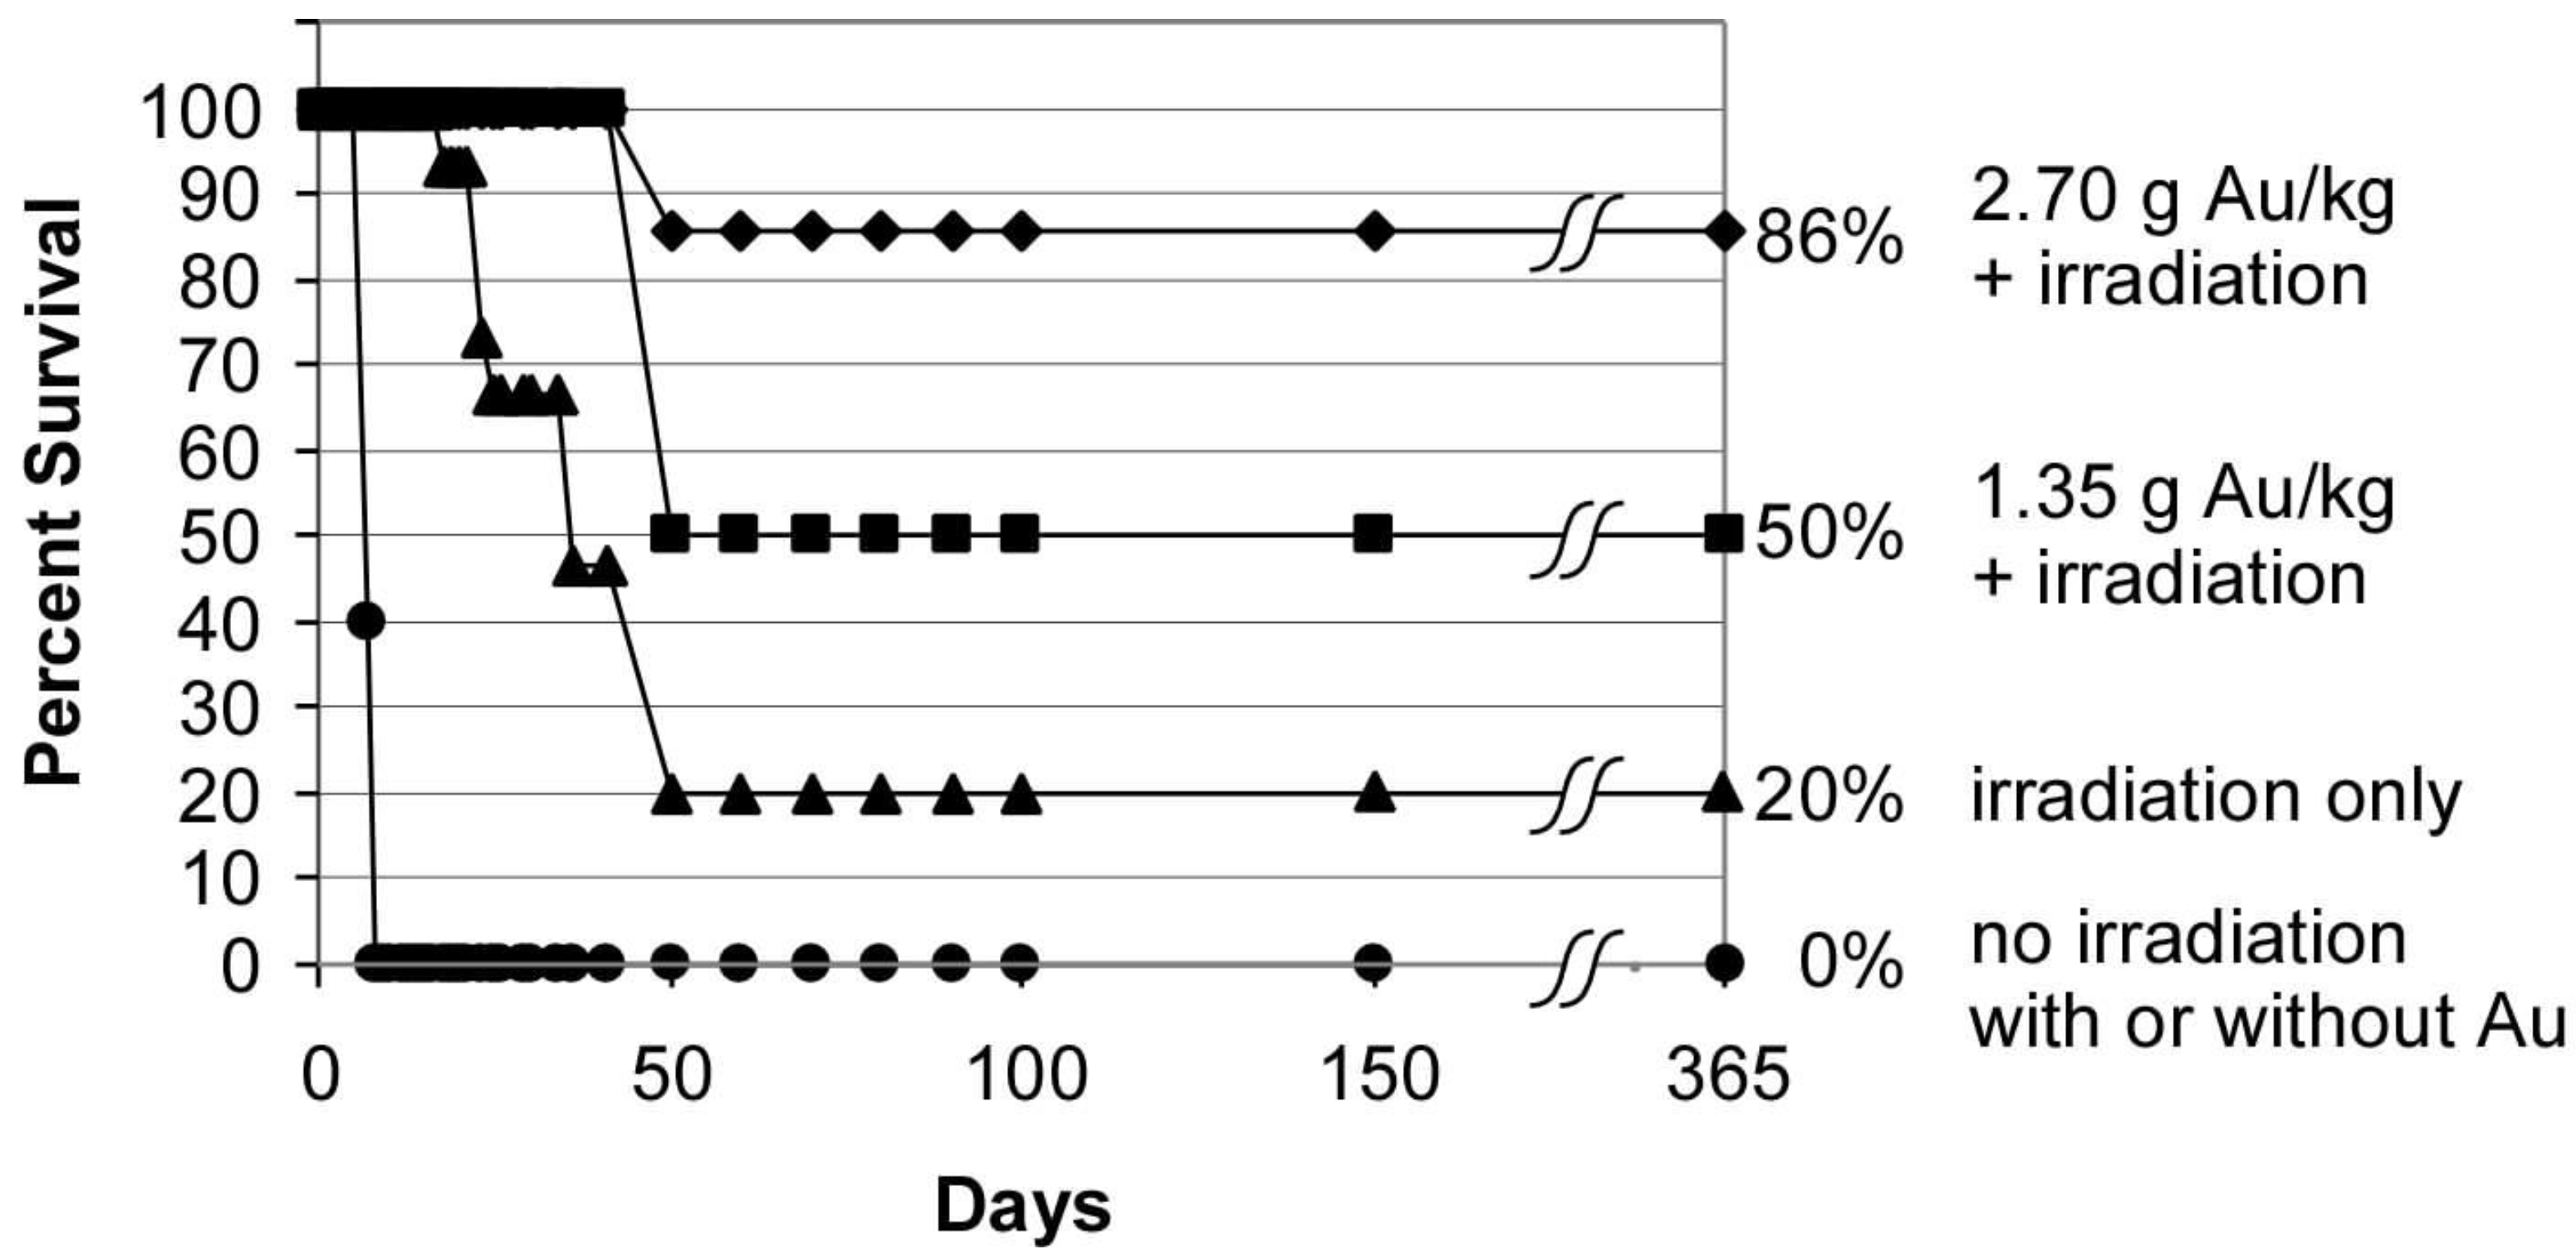

1.2. Gold Nanoparticle Imaging and Radiotherapy

1.5. Iodine Nanoparticle Glioma Therapy